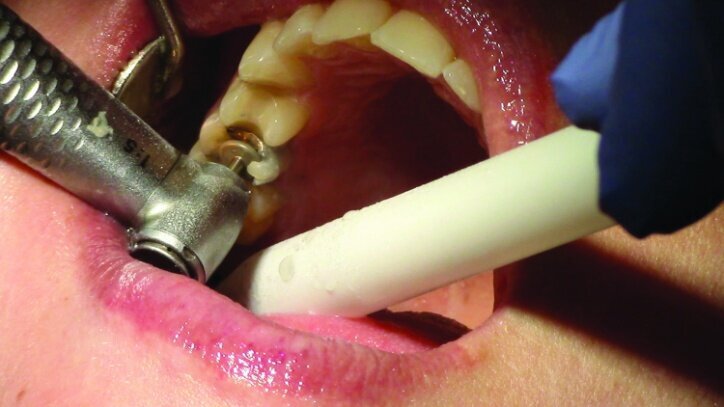

Depth guide cuts were made using a 330 bur, which has a 2 mm cutting surface (Figs. 2a–3b). This ensures 2 mm of occlusal reduction to accommodate 2 mm of material thickness on the occlusal surface of the restoration.

Gross occlusal reduction was completed using a KS7 bur to the depth cuts (Figs. 4–8b, 9c). Adequate clearance was verified with a 2 mm prep check from Common Sense Dental Products.